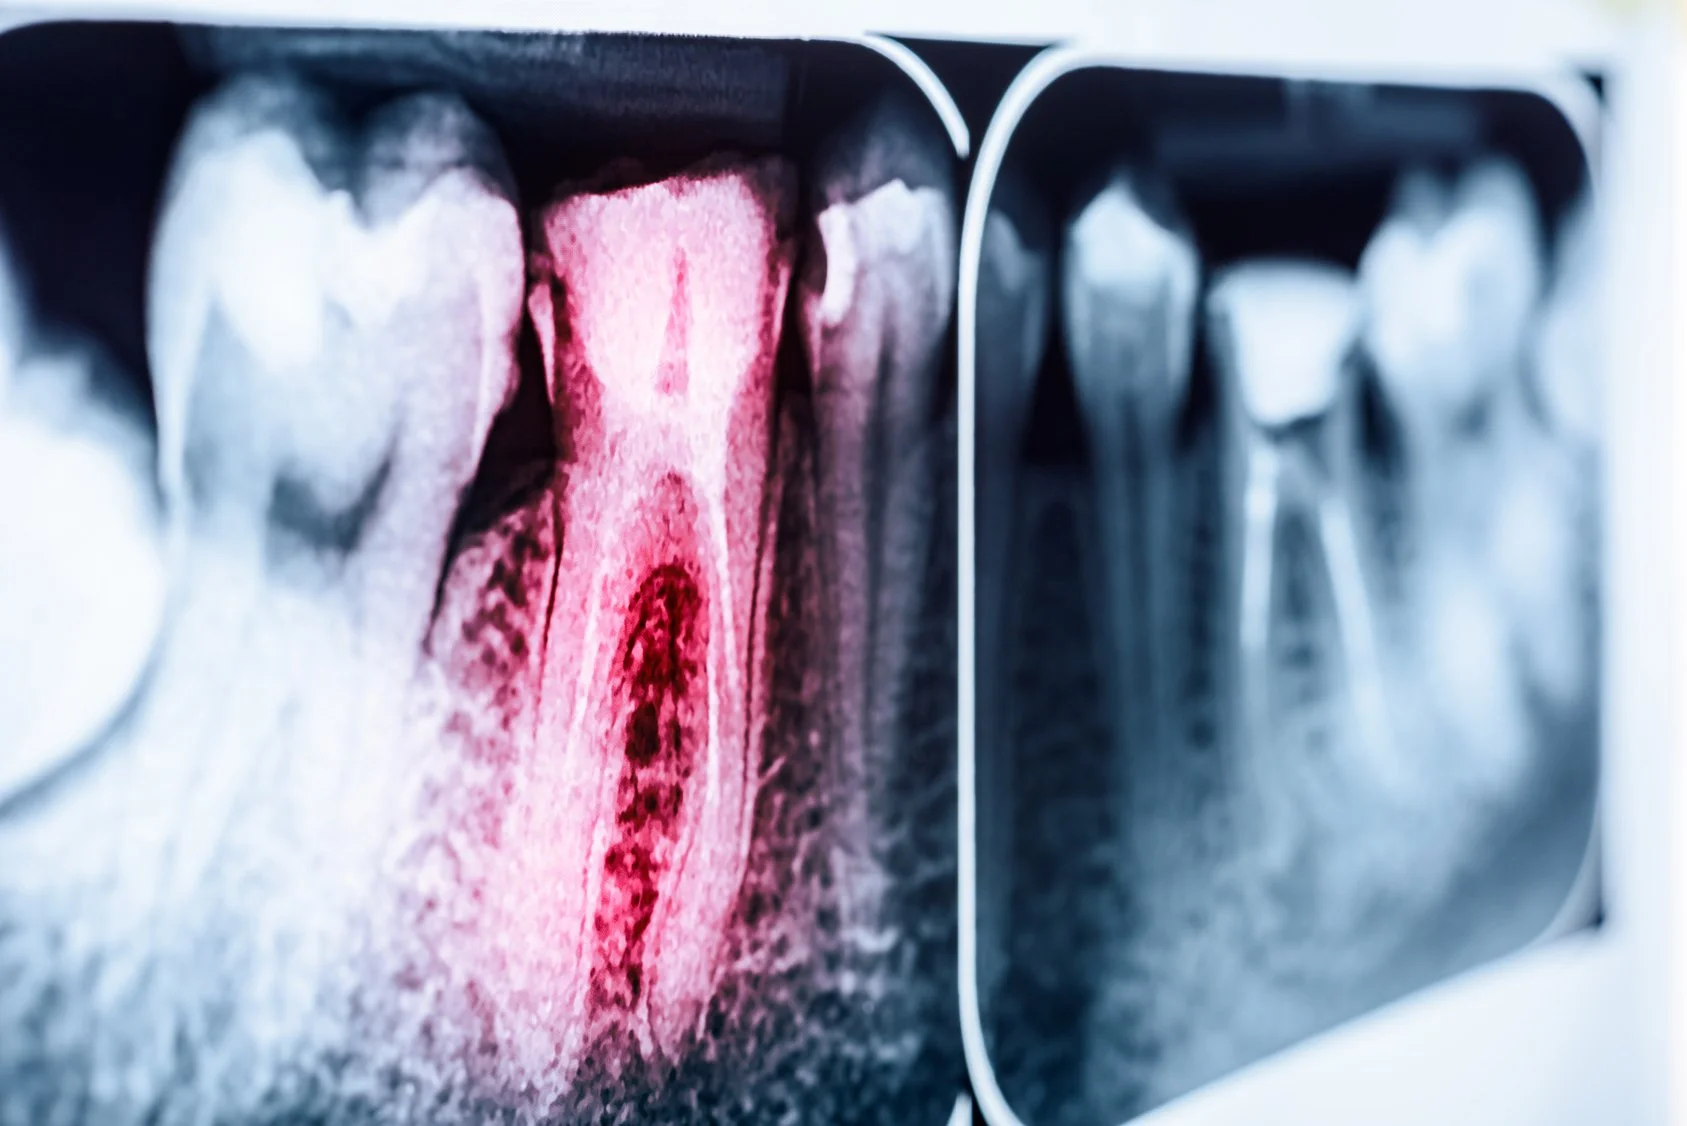

Dental X-rays, particularly in childhood, have been linked to an increased risk of the most common brain tumor in adulthood. Dr. Elizabeth B. Claus, an epidemiologist at the Yale School of Medicine in New Haven, Conn., and at Brigham and Women's Hospital in Boston, led a study that found a strong connection between mouth X-rays and tumors called meningiomas.

Even just having the typical once-yearly bitewing X-rays, which expose a small piece of film placed between the teeth to a beam of radiation, raised the risk for meningiomas significantly. Panoramic X-rays that sweep around the head to grab a view of all the teeth -- often to assess the need for braces -- nearly quintupled the risk of developing a meningioma if performed before a child's 10th birthday!

I used the same protocol I had been using on my children, but added a number of additional supplements and targeted homeopathics to do whatever I could to save this tooth from being pulled. And, it worked. That was several years ago, and in the most recent check-up, I decided to have a digital sensor x-ray, which has a 90% reduction in radiation dosage. I personally do not recommend any type of xray for anyone, unless absolutely critical to health, and the benefits outweigh the risks. In my case, I had to be certain that an infection or some sort of bone or tooth loss was not occurring under the surface of the filling, that could compromise my health down the road. So I underwent my radiation protective protocol before visiting my dentist, and continued with a radiation cleansing protocol afterwards, to give my body the best possible support I could to deal with the radiation.